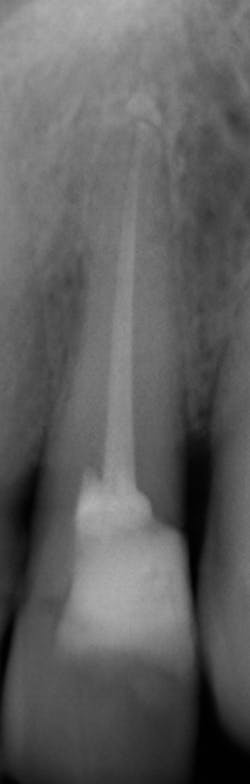

What’s unique about this system is that it uses nanotube technology to capture standard 2D images (figure 2) and gives you the option of taking a tomosynthesis image, which captures multiple images from several angles (figure 3). Images are compiled into a sliced volume and dissected into 0.5 mm or 0.1 mm slices that you can scroll through, rotate, enlarge, measure, and adjust. The system can “un-overlap” many teeth; this is convenient because with regular 2D x-rays, I had to retake the image at different angles and often with little success.

In fact, twice today I was able to see something with Portray that wasn’t visible in the original 2D x-ray (figure 6). I don’t always take 2D images now, but I do when I think the case is straightforward or the patient has very little dental history. I often end up taking a tomosynthesis image just to be safe. With the 3D image I can scroll from buccal to lingual through the tooth and get much more data (figure 7). The new system has replaced my 2D PAs and bitewings.